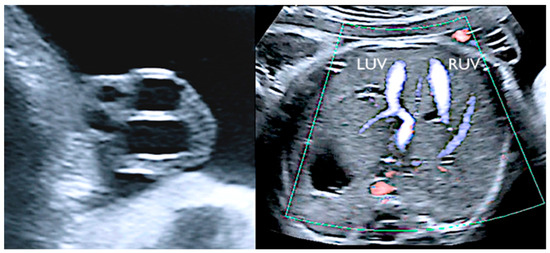

3.4. Single Umbilical Artery